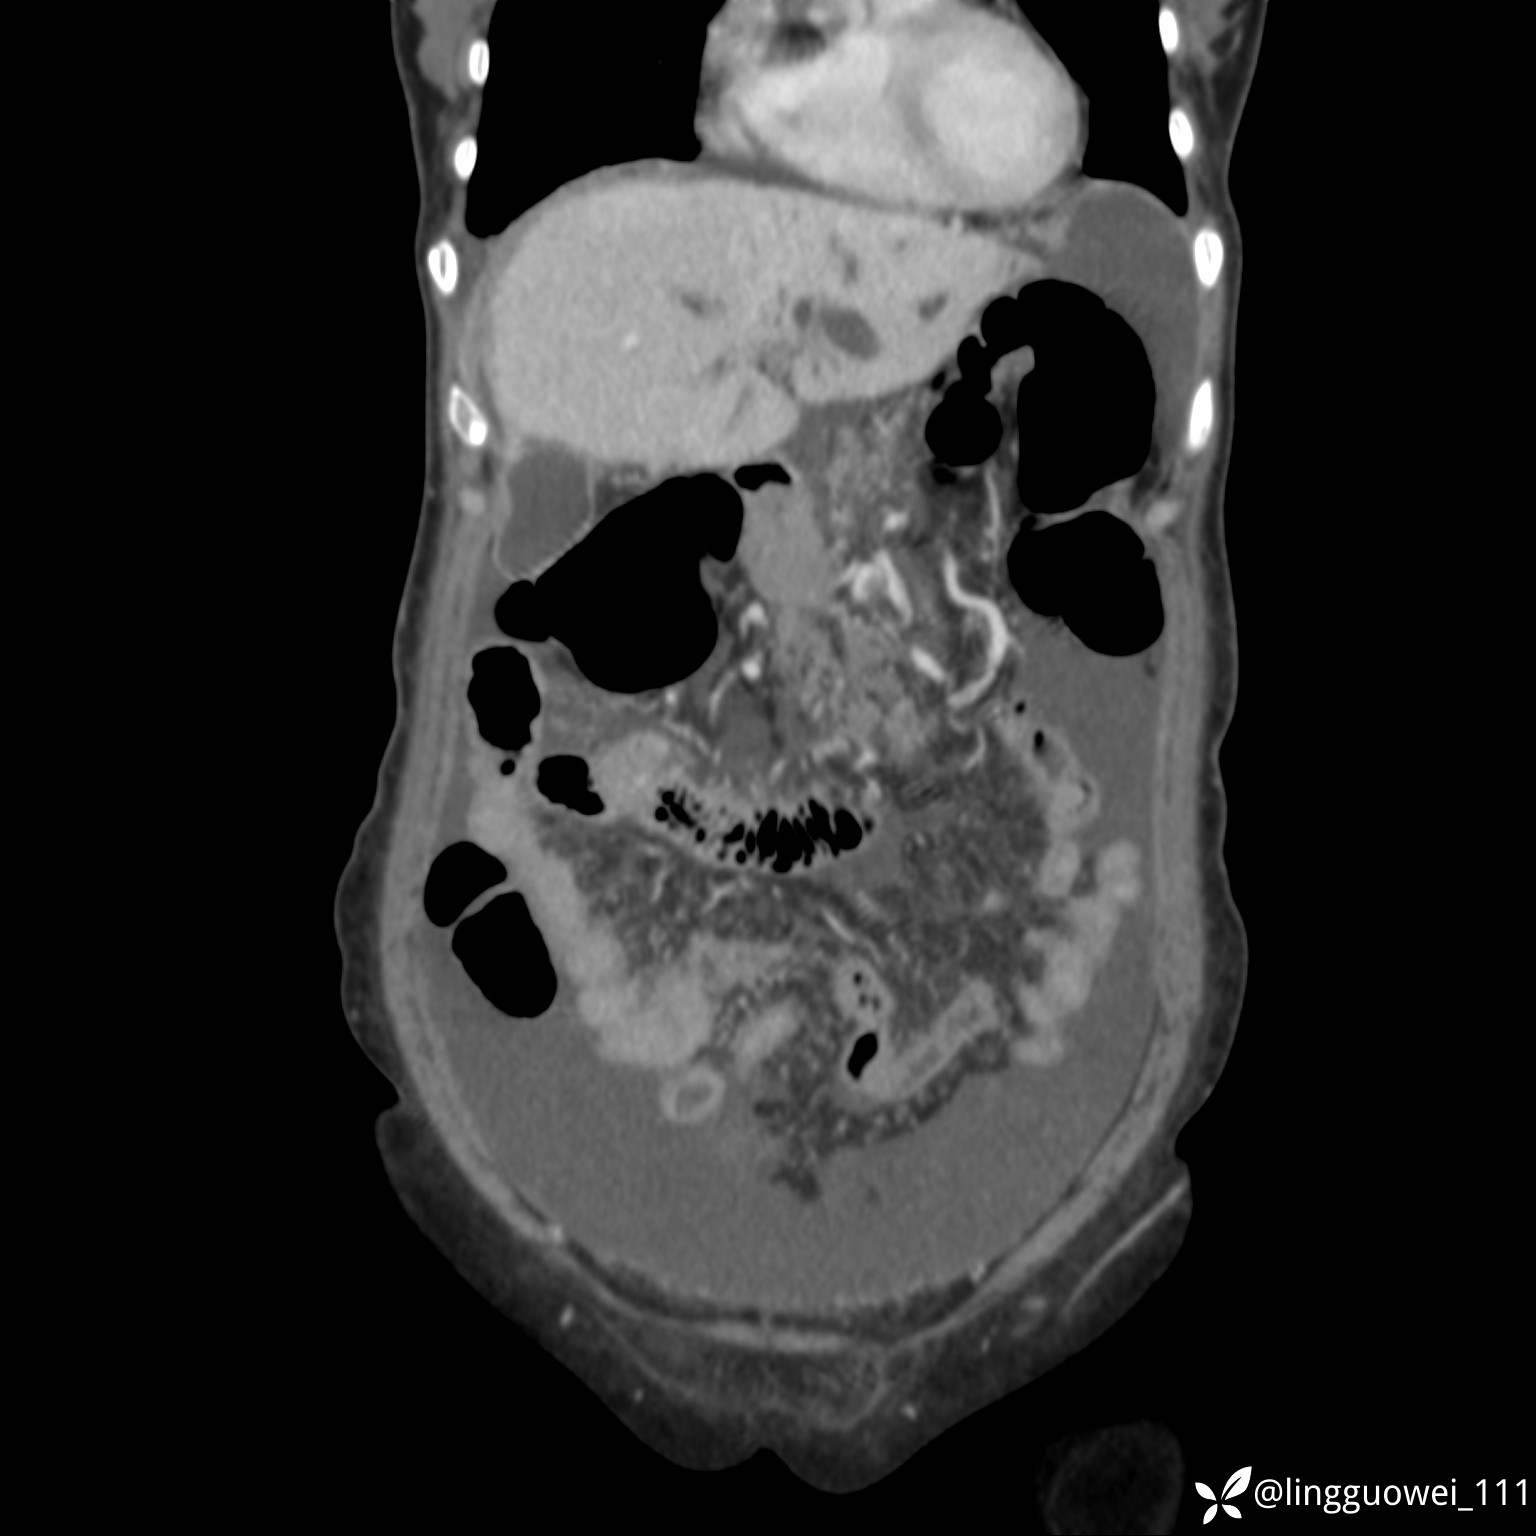

病例女,65岁,门诊行胃肠镜检查后,说腹胀入院检查,CT能发现病因吗?已公布结果

患者性别:女

患者年龄:65岁

主诉:门诊行胃肠镜检查后,诉腹胀,入院检查,肝有病变吗?腹膜及腹腔的表现有特征性吗?

增强动脉期: